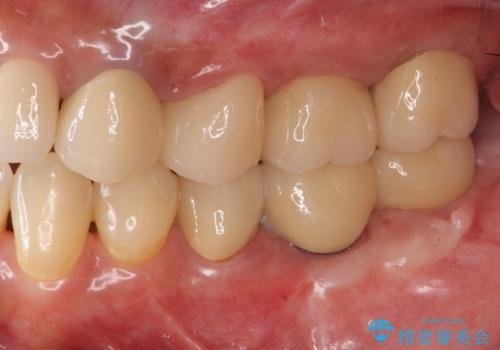

抜歯後、インプラントを用いて咬合機能を回復すると共に周囲に強固な角化歯肉を移植することによりより長期にわたり安定したインプラント周囲環境となるよう治療を計画します。

- 83.6万円(インプラント×2・アバットメント×2・クラウン×2)費用は治療当時の料金となります

インプラント周囲の角化歯肉が存在することにより、歯ブラシがしやすくなりインプラントにトラブルが起きる確率を減らしより長期的な予後を望むことができます。